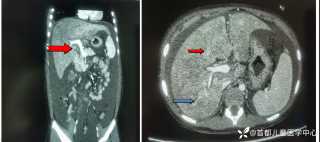

玩耍被撞后10岁男孩被诊断有肿瘤,多器官切除 当地卫健局:医院存在问题,已立案

2023年10月26日,来自山东菏泽市成武县的小烨和他家人的命运被彻底改变了。这个原本阳光、可爱的小男孩在一次意外被撞击后,在医院检查出了腹腔内存在肿瘤,并在手术中被切除了包括十二指肠、胰腺、大部分胃和小肠等多个器官。此后便无法再像正常人一样吃饭、喝水,活着要靠长期静脉注射营养液。一份2024年12月由第三方机构出具的司法鉴定意见书显示,当时给小烨做手术的成武县人民医院在该医疗行为中存在过错,与小烨的损害后果之间存在因果关系,建议医疗过错在损害后果中的原因力大小为同等原因。此外,另一份由成武县卫生健康局在2025年9月28日发出的书面答复中显示,成武县人民医院存在24小时内未完成病历;手术知情

目前知道的消息,第一,术前发现一个血肿,然后做增强CT发现一个占位,没说血肿与肿瘤的关系,术后病理没有描述肿瘤出现破裂出血,大概率就一个小血肿,我就不明白当地主任凭哪个指针去给这小孩开急诊刀的?哪个指南告诉他需要急诊开?第二,诊断不明确他想的不是进一步检查,一边观察一边进一步查,他反而选择腹腔镜探查,这个探查的指针在哪?第三,腹腔一个血肿,没有活动性出血,没有血压心率出现问题,为什么要开腹进去碰它?不能等血肿吸收再明确肿瘤性质吗?第四,1点进腹,3点病理结果出来,按这个时间还算顺利,应该还没出事,孩子还算平稳,病理是低度恶性,切了就治愈,他一年能开几台这手术,就敢继续做,拿孩子练手。第五,后面